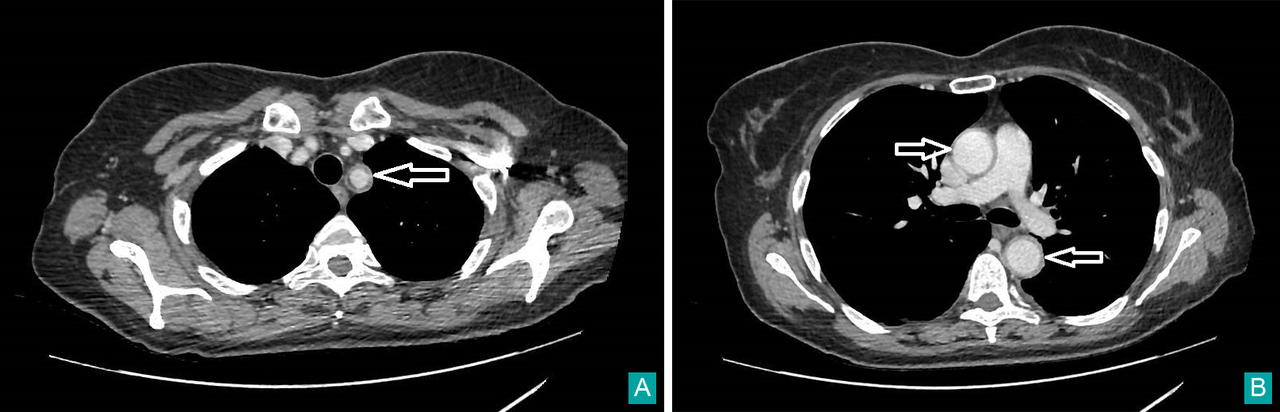

Il s’agit de céphalées matinales d’évolution progressive depuis un mois devant faire évoquer une hypertension intracrânienne et toutes ses causes (y compris une thrombose veineuse cérébrale), une méningite chronique, une hypertension artérielle incontrôlée, ou une artérite a cellules géantes.